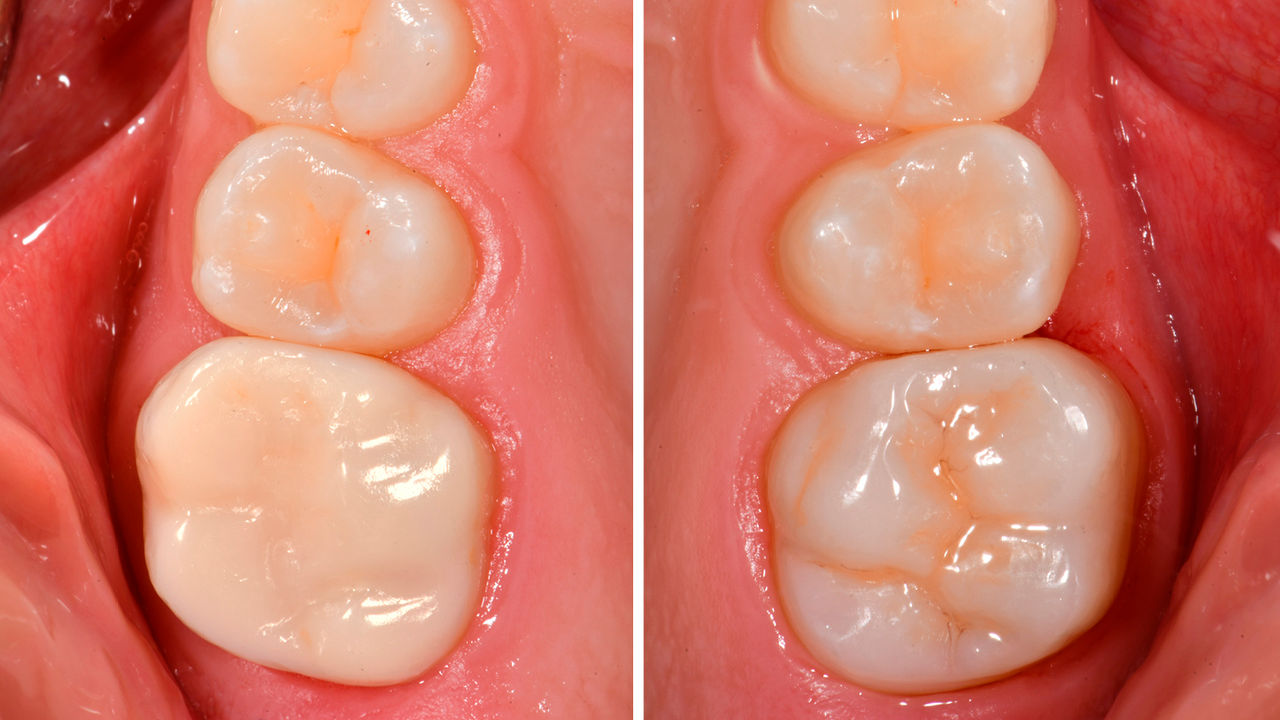

Restauration des dents MIH avec CEREC Tessera

Une couronne CEREC Tessera

Situation initiale du patient :

La patiente s’est présentée avec une sensibilité croissante à la température au niveau de ses molaires dès six ans. L’anamnèse n’a révélé aucun signe de malformation de l’émail associée à un médicament ou à une maladie. La grossesse de la mère s’est déroulée sans complications. L’examen clinique a révélé une perte de substance importante et un émail hypominéralisé englobant la totalité des couronnes cliniques des dents 16 et 26. En outre, l’incisive centrale gauche et les deux premières molaires mandibulaires étaient affectées par des hypominéralisations. La dent 21 n’avait pas de cavité et ne présentait pas d’hypersensibilité. Les premières molaires mandibulaires présentaient de petites cavités avec une hypersensibilité. Sur la base de ces résultats, le diagnostic a été posé : hypominéralisation molaires-incisives (MIH). Selon l’indice MIH-Treatment-Need-Index [Bekes & Steffen 2016], les dents 16 et 26 ont reçu un score 4c nécessitant une couverture complète par des couronnes. La dent 21 a reçu un score 1 et a été laissée en l’état à la demande de la mère et de la patiente elle-même. Les dents 36 et 46 ont reçu un score 4b et ont été soignées avec des restaurations directes en composite.

À ce point, les molaires maxillaires n’étaient pas encore complètement sorties. Par conséquent, initialement, ces dents ont été soignées avec des restaurations directes en composite en attendant la sortie complète des dents. À l’âge de 11 ans, les dents 16 et 26 étaient complètement sorties, ce qui a permis de réaliser des restaurations avec des couronnes complètes.